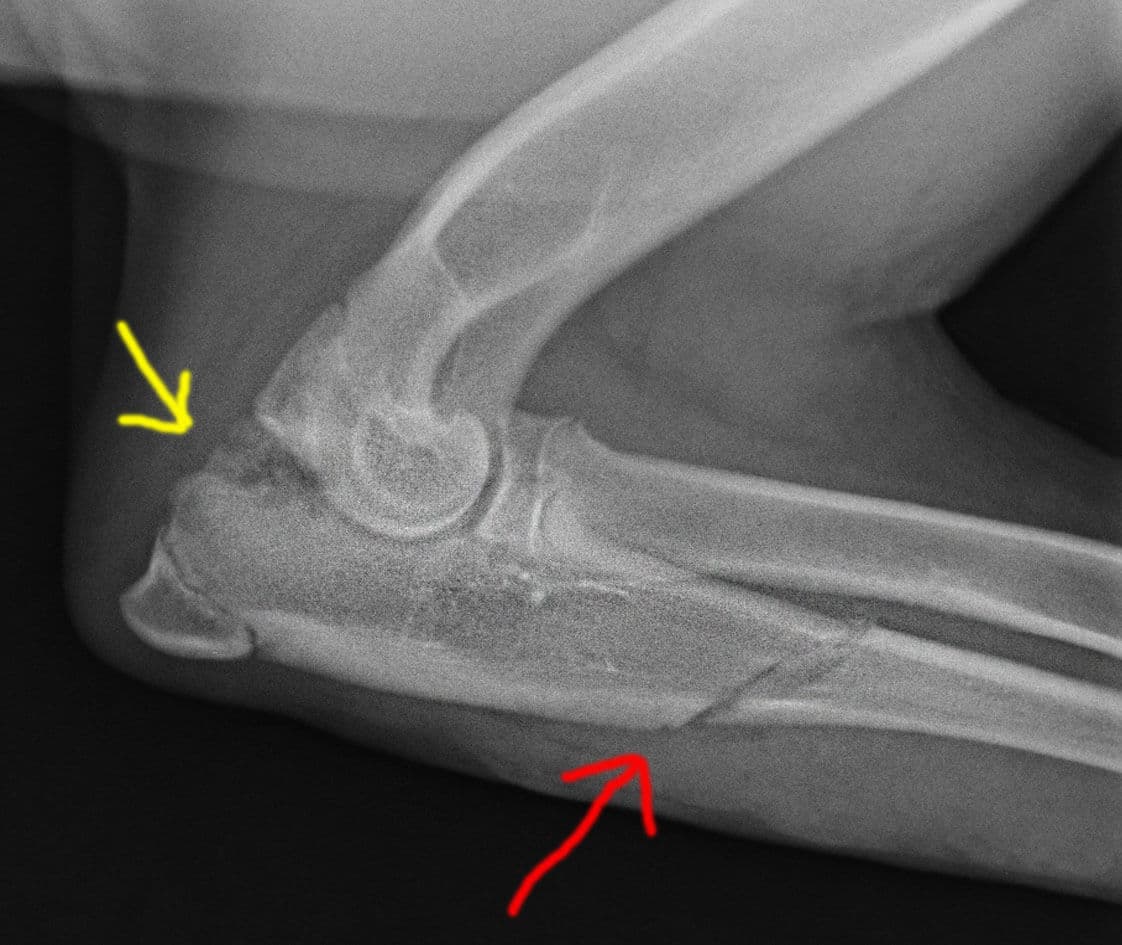

Кане-корсо 5 месяцев. Диагноз: фрагментация крючковидного отростка.

Рекомендована операция ДДОЛ.

Операция ПБОЛ в возрасте 6.5 мес. Красная стрелка: зона распила;

желтая стрелка: практически лизированный крючковидный отросток.